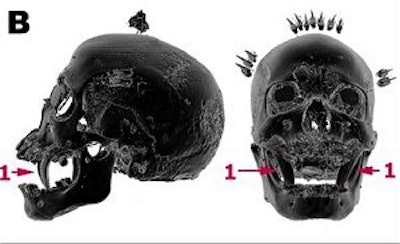

| A 19th century Ekoi head from Nigeria made of bone, teeth, cloth, clay, wood plant fibers, skin, and claws with a height of 26 cm (A). In B, CT surface-shaded display (SSD) views in which the structures of lower density than bone have been erased, revealing that the incisors of a carnivorous animal (1) have been inserted in the upper jaw of a human skull. |

| In C, a selection of thin axial slices, which illustrates the original technique used to make the head. The nasal cartilage was replaced by a piece of carved wood (2) and covered with antelope skin; the orbits (3) were filled with cloth; the temporal fossae were filled with clay (4) and sticks (5), finely carved to give the impression of scarification. These were inserted under the taut antelope skin. The articulated wooden tongue is attached to the top of the wicker work by a fiber ligature (6). The cavity of the right frontal sinus is filled with a magic charm (7) covered by clay and antelope skin. Images courtesy of Dr. Marc Ghysels. |